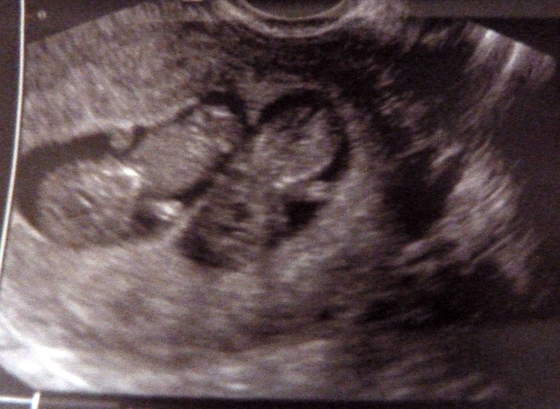

stokrotta śliczny-widać już rączki :-) mój też już wymachiwał :-)